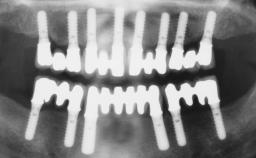

Conventional Loading of Six Implants in the Mandible and Final Restoration with a Full-Arch Metal-Ceramic FDP

# of Implants 6

Type of Implants One-Piece

Attachment One-Piece

Prosthesis Type FDP

Defining Characteristics Fully edentulous lower jaw to be rehabilitated with two or more implants

Modality > 4 implants, extending to mental nerve region

Retention Screw-retained, with 4 or more splinted implants Screw-retained, with 4 or more splinted implants